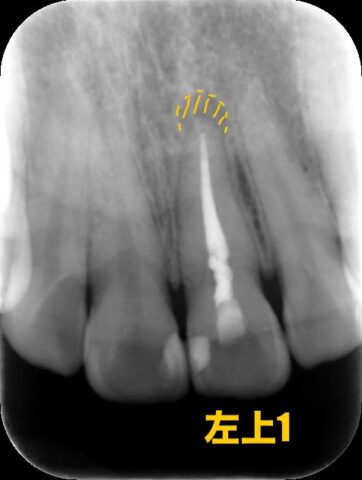

デンタル写真やCT写真でも見てみましょう

根っこの先に膿が溜まってしまっています。

現在症状などはないそうですが、根管治療のやり直しが必要となります。